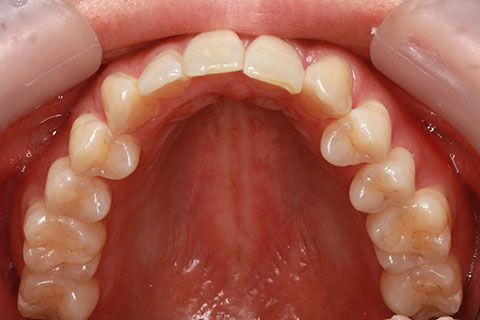

ハーフリンガル矯正3(上の歯のみ舌側矯正で治療)

治療前

治療中(開始直後)

治療中(開始半年後)

治療後

- 年齢・性別

- 25歳女性

- 治療期間

- 2年0ヶ月

- 抜歯

- 上下4番抜歯

- 治療費

- 110万円

- 備考

- 治療内容

- 施術の副作用(リスク)

- 表側矯正と比較して、力学的な操作性が複雑なため、ボーイングエフェクトを起こしやすい。